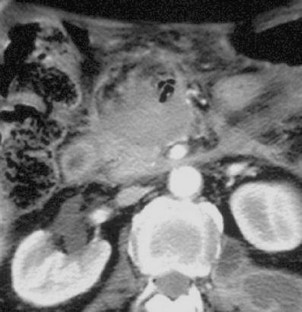

Combined percutaneous thrombin injection and endovascular treatment of gastroduodenal artery pseudoaneurysm (PAGD): case report

A 69-year-old man with a history of acute pancreatitis developed a huge pseudoaneurysm of the gastroduodenal artery (PAGD), as diagnosed by CT scan. The PAGD was treated by percutaneous thrombin injection (2,000 IU) under ultrasound guidance and selective embolization of gastroduodenal artery with microcoils with its complete exclusion. The 6-month follow-up confirmed the complete exclusion of the PAGD sac.

Fig. 2